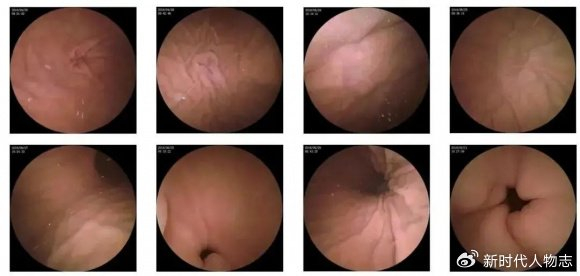

肛門(mén)息肉早期圖片展示

(請(qǐng)?jiān)诖颂幉迦敫亻T(mén)息肉早期圖片)

圖片展示可以幫助公眾更直觀地了解肛門(mén)息肉的外觀和癥狀,請(qǐng)注意,由于個(gè)體差異和拍攝角度等因素,圖片僅供參考,不能作為診斷依據(jù)。